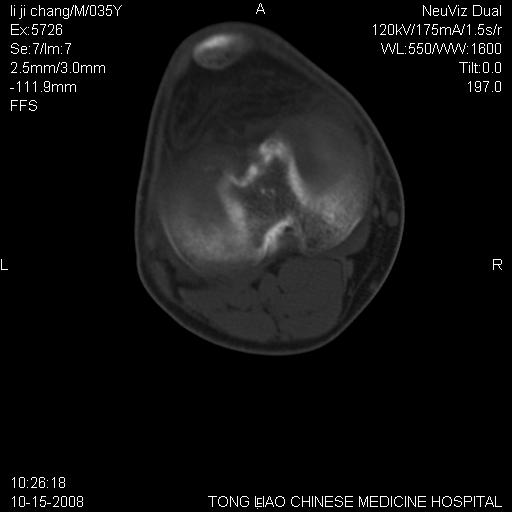

男,35岁,骨科诊断骨性关节炎。继往使用过激素,现股骨头坏死。膝关节病变,请会诊

一元论-----亦考虑为坏死

支持考虑无菌坏死

支持无菌坏死伴退行性骨关节病.

剥脱性骨软骨炎:是一种关节下软骨及软骨下骨缺血性坏死。

支持 无菌性坏死伴退行性骨关节病。

支持无菌坏死伴退行性骨关节病